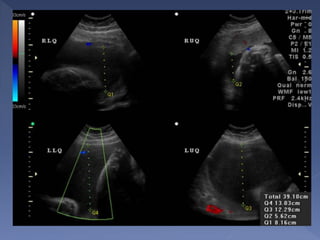

 Most reproducible/accurate

 Technique(4 quadrant technique)

Divide the uterus into four quadrants using the

linea nigra as the vertical axis and the

umbilicus as the horizontal axis.

 Linear transducer head placed along mother’s

longitudinal axis and held perpendicular to the

floor in the sagittal plane.

The pocket with the largest vertical dimension

is measured in each quadrant.

Sum of all four measurements = AFI

 Cord or extremities may traverse the

pocket, but may not be measured as

part of the vertical depth

 Values

<5cm = very low (oligohydramnios)

5-8cm = low

8-25cm = normal term AFI

>25cm = polyhydramnios

• Excessive transducer pressure

• Cord-filled pockets should not be used

• Obese patients may introduce scatter

that creates artifact echoes

– May overcome with lower frequency

transducer

• Not measuring low in the uterine cavity